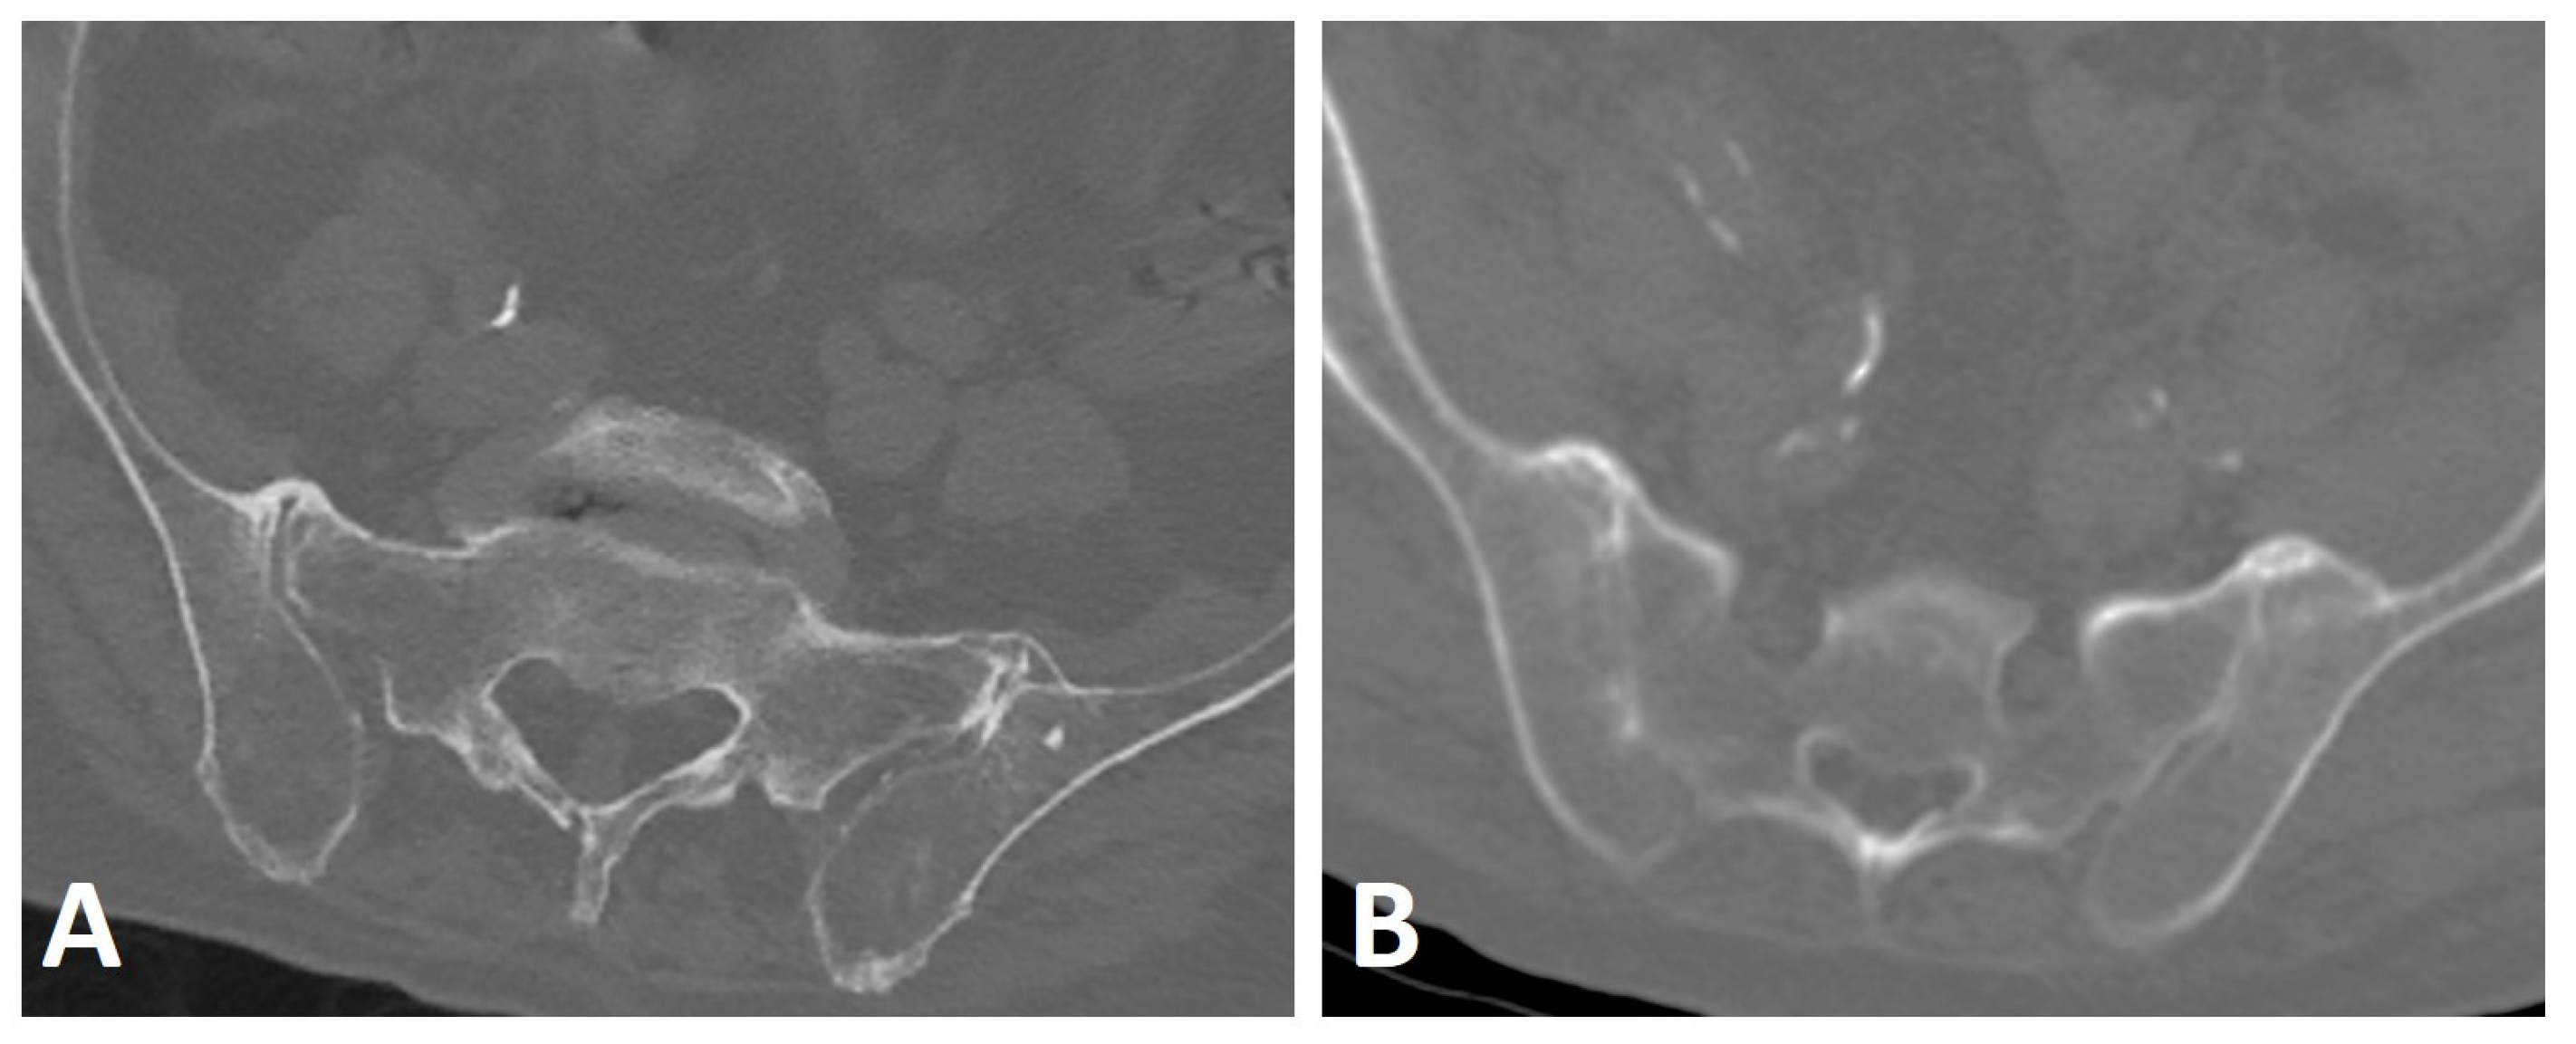

To distinguish between SpA and DISH, the SIJs appear as an exclusion criterion in the Resnick and Niwayama criteria, so that findings compatible with sacroiliitis, such as erosions, sclerosis, and ankylosis of the SIJ on pelvic radiographs, preclude the diagnosis of DISH [1]. In subsequent studies, Resnick and co-workers described the presence of SIJ osteophytes, para-articular bony bridging, and coexisting osteoarthritis on pelvic radiographs of subjects with DISH [4,66]. Over time and with advances in imaging technology, the characterization of SIJ involvement in DISH has been refined for both CT and MRI. Extra-articular bridging osteophytes located ventrally to the SIJs, similar to flowing osteophytes in the spine, are commonly seen in DISH patients, resulting from enthesopathy of the involved ligament (Figure 7A) [67,68]. This anterior SIJ bridging overlying the SIJ on pelvic radiographs obliterates the joints, resulting in a false diagnosis of SIJ ankylosis, and thus SpA [67,69]. Indeed, studies evaluating the SIJs of subjects with DISH on CT have shown that anterior bridging of the SIJ is a common finding [70,71], but in contrast with the Resnick and Niwayama criteria, both intra-articular and posterior entheseal ankylosis are also prevalent in DISH (Figure 7B) [70,71].

Figure 7.

Axial CT images of the SIJs of two patients with DISH. (A) Characteristic extra-articular bridging osteophytes are seen anterior to the SIJs. (B) In addition to the ventral extra-articular osteophytes, clear ankylosis can be observed within the right and left SIJs.